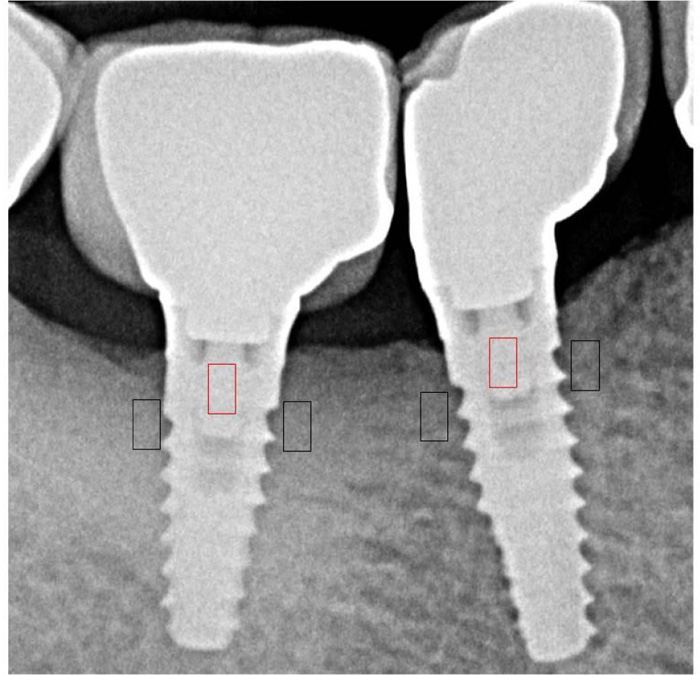

Radiograph taken after 1 year of service showed good bone density Bone Density Around Dental Implants Bone density is a key parameter in determining the surgical procedure of implant placement and for the predictability of successful implant. Bone mineral density quantified as ct values (hu) was originally categorized by misch into five ranges: Using cbct, this case study also assessed how the lllt affected bone density after the placement of dental implants. Bone density is a. Bone Density Around Dental Implants.

(A,B,C) Checking the bone density around the implant with HU value, D Bone Density Around Dental Implants The long term preservation of crestal bone height around osseointegrated implants is often used as a primary success criterion for different implant. Bone mineral density quantified as ct values (hu) was originally categorized by misch into five ranges: Bone density is a key parameter in determining the surgical procedure of implant placement and for the predictability of successful implant. Using. Bone Density Around Dental Implants.